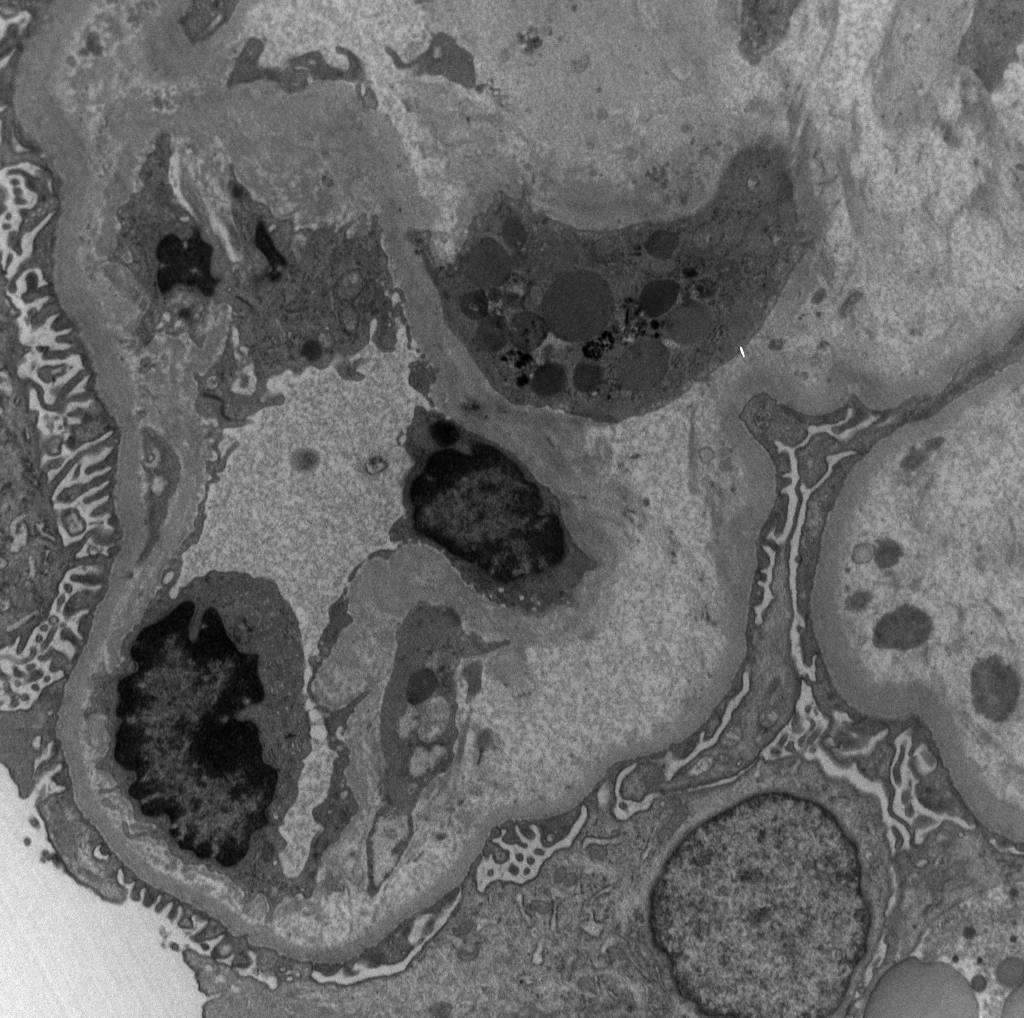

Long weekend often brings urgent cases. Here is one that was STATed, ended up showing anti-GBM GN. Diffuse crescents (nearly 100%). Linear IgG. #RenalPath